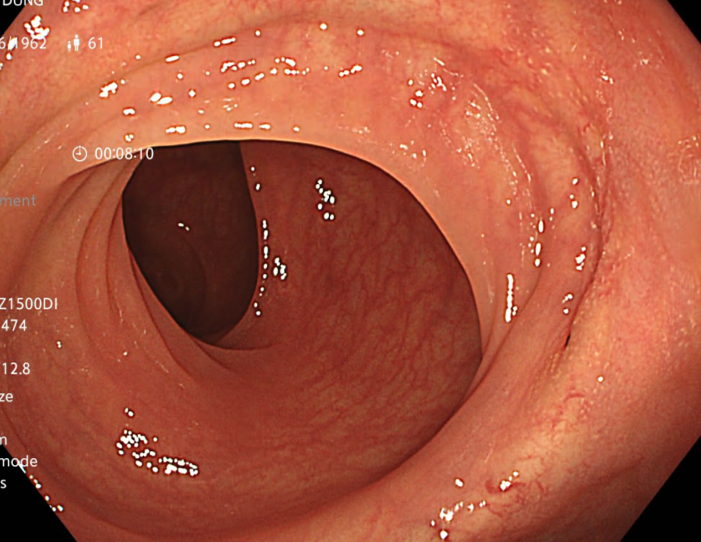

Người bệnh được tiến hành nội soi đại tràng với kết quả: các tổn thương lồi ở đại trực tràng đã biến mất, niêm mạc đại trực tràng bình thường

Hình 3: Hình ảnh đại tràng sigmoid và trực tràng sau điều trị